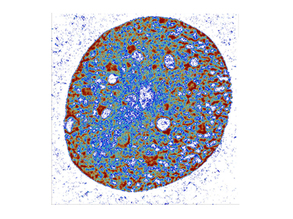

Brain-damaging Sepsis

15